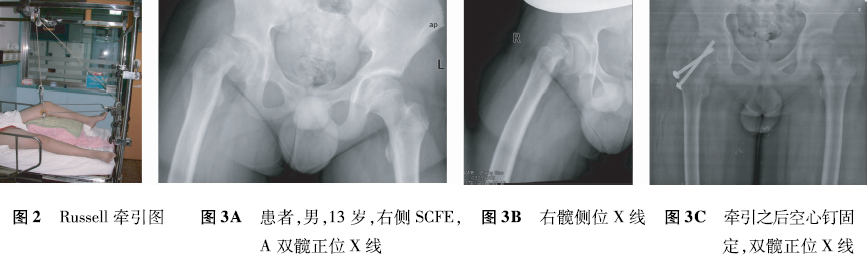

2.Russell牵引之后经皮空心钉固定

在股骨髁上行骨牵引,然后通过2个方向的牵引在股骨干长轴上形成合力,这样既能达到较大的牵引力量,又能通过牵引针调整下肢旋转角度,利于复位和术后功能改善(图2)。牵引时间多为3周,每周逐渐增加内旋。然后在麻醉满意后,上牵引床行经皮空心钉内固定(图3A~F)。